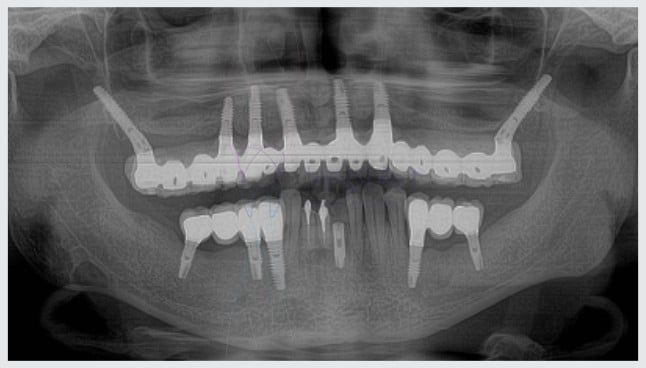

Em geral para a técnica de implantes zigomáticos são inseridos entre 2 e 4 implantes. O número mínimo de implantes para reter uma prótese fixa é quatro (implantes all on four).

Além disso os cilindros de implantes utilizados na técnica zigomática são de três a quatro vezes maiores que os implantes normais.

Não encontro no google imagens rx periapical de implantes zigomáticos pra ver a osseointegração dos implantes zigomáticos, e como pedir pro radiologista PERIAPICAL (Indique a região) já que fica no osso zigomático.

Não existe periapical para implante zigomatico, mesmo porque periapical é de dente. O implante zigomatico não tem osteointegração, é um osso cortical, tem muita carga e depois de uns 10 anos ele simplesmente se “solta” do osso, por isso é indicado como última opção.

Entendo perfeitamente suas preocupações sobre a manutenção e o suporte para implantes zigomáticos. A manutenção envolve higiene rigorosa e visitas regulares para limpeza profissional e avaliação da prótese, que pode ser removida para inspeção detalhada dos componentes (parafusos, abutments) e limpeza. O desgaste é observado clinicamente com a remoção da prótese e confirmado por radiografias como a panorâmica.

A questão da emergência e compatibilidade de peças é crucial: cada marca de implante tem componentes específicos, o que pode dificultar o atendimento rápido se o profissional não trabalha com a sua marca. É fundamental saber a marca dos seus implantes e ter um plano de contingência. Para esclarecer todas as suas dúvidas e oferecer a segurança que você precisa, convido você a agendar uma consulta em nossa clínica. Assim, poderemos avaliar seu caso individualmente e apresentar as melhores soluções para sua tranquilidade.